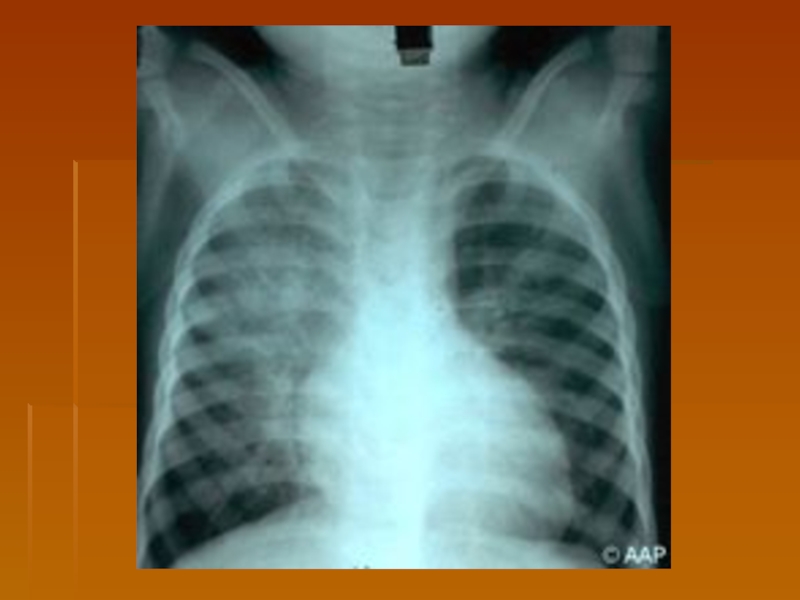

Слайд 19Copyright ©2006 American Academy of Pediatrics

Дифтерия переднего отдела носа